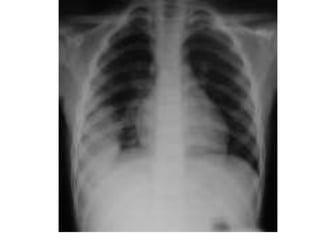

• Chest X-ray PA view showing trachea is

central, lung fields are clear, both hilum are

normal, mediastinum is normal, cardiac

shadow is normal in size and contour, both

costophrenic and cardiophrenic angles are

clear, diaphragm is normal in shape and

position, bony skeleton and soft tissue

shadows are normal.